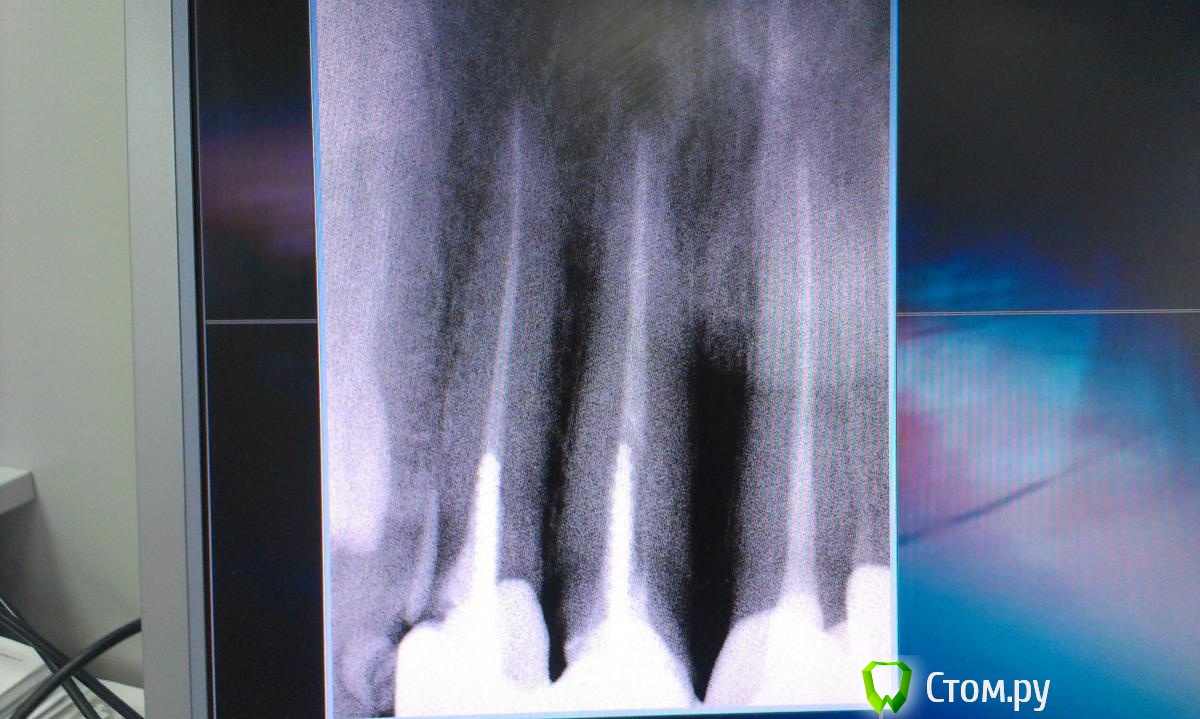

Ольга97-99 Опубликовано 6 сентября, 2014 Поделиться Опубликовано 6 сентября, 2014 Добрый день, уважаемые стоматологи. Прошу помощи... Ситуация с зубами плачевная... Не буду долго расписывать о том, как с 10 лет я не вылезаю из кресла стоматолога. Леченые зубки в небольном городе Н. Постоянно выпадающие пломбы, приводящие к повторному лечению. Депульпированны практически все. Периодичность посещения стоматолога - 3 мес., + манипуляции парадонтолога. Но к 26 годам имеем нижепредставленное.. С задними зубами все более или менее ясно - еще несколько на удаление, затем имплантация. С передними верхними... МК коронкам 7лет. Не беспокоят, боли, дискомфорта нет. Но эстетика оставляет желать лучшего. Еще, как говориться, не везет так не везет - улыбка десневая. И поднявшаяся синюшная десна во всю сияет. Было решено - настало время перемен. Мой обход ортопедов в нашем славном городе начался с мыслью вдохновляющей "заменить мк на дц". Более натуральный вид, к тому же рецессия десны должна была остановиться, так Интернет и доктора говорили )). Что имеем сейчас, мнения двух (на мой взгляд самых адекватных спецов) ортопедов: Первый: снимаем коронки, смотрим состояние корней. Если все нормально, штифты не трогаем, меняем пломбы и делаем дц. Но 80-90% вероятность, что корни испортились, либо будут повреждены (при снятии коронки выйдет штифт, разрушив корень). Тогда удаление, затем имплантация. Не буду портить мнение о себе и писать, что я испытывала после такого вердикта.... Второй: (его, кстати, посоветовал 1й) глянул (бегло) на мой снимки, говорит: снимаем коронки, вынимаем штифт, лечим каналы, делаем вкладки из дц, делаем коронки из дц. На мой вопрос "а если корень поврежден? или еще что-то не так пойдет" был ответ "зачем тебе это все знать, я доктор и я говорю тебе - будут коронки нормальные". Думаю, не стоит уточнять, что гарантий по сроку службы новых коронок я не услышала. Ну верней, прозвучала классика про кирпич на голову. Понятно, какой вариант мне запал в душу, и чего я бы хотела.. Но я могу хотеть одного, а реальность может быть совсем другой.. Не имею право на неоправданный риск, это же передние зубы... Пожалуйста, посмотрите снимки. Можно услышать Ваше мнение насчет возможности замены протезов передних верхних зубов. Заранее спасибо!!! Ссылка на комментарий

Korel Опубликовано 8 сентября, 2014 Поделиться Опубликовано 8 сентября, 2014 Вопрос о состоянии корней остается открытым до момента снятия коронок, я правильно понимаю? Нет, не правильно. Ваши корни видны на R-снимке. Открытым остаётся вопрос о состоянии культей скрытых коронками. 1 Ссылка на комментарий